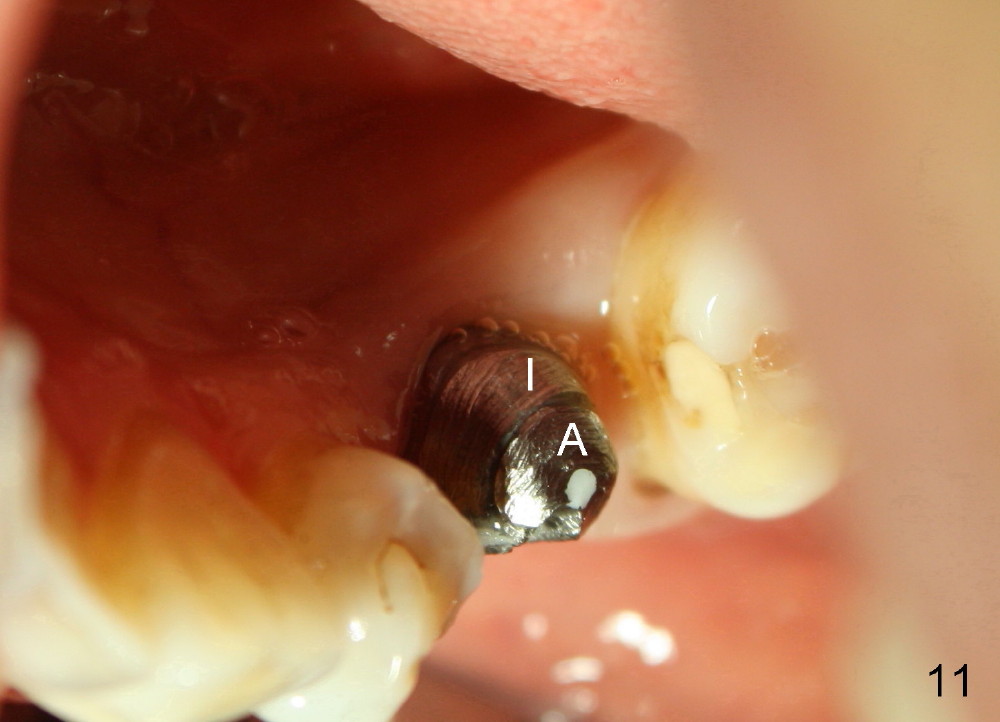

Taking multiple intraop X-ray is also necessary for depth adjustment (Fig.3-5). For example, when a 5x20 mm tap is inserted at the depth of 17 mm, it is close to the mental loop (Fig.4), whereas the binding to the bone is minimal. So a larger implant is to be placed at a shallower depth (Fig.5: 6x17 mm with insertion torque >60 Ncm). The shallower implant placement creates limited space for future abutment and crown (Fig.6,7). A short abutment will be used and the implant margin will be prepared as low as possible. As expected, the wound heals in a week (Fig.8).

Six months postop, bone density around the implant increases (Fig.9). There is slight gingival recession buccal to the implant (Fig.10 arrow). A short abutment is placed and prepared short (Fig.11 A); the margin is prepared as low as possible in the implant (I).